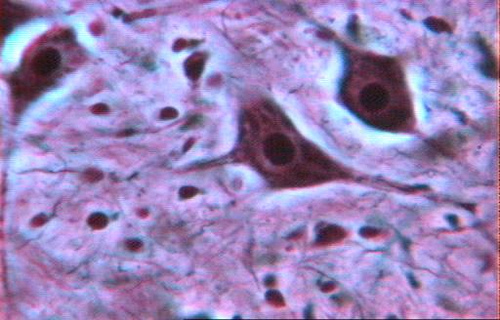

Forma: Tienen aspecto de arañas con largas patas. A través de los canalículos óseos, los osteocitos se comunican entre sí. La unión entre osteocitos se hace a través de uniones ‘GAP’.

Son células polinucleadas de gran tamaño derivadas de la fusión de monocitos.

Son las células responsables de la resorción de la matriz ósea. Se encargan de eliminar hueso, tanto matriz ósea mineralizada como orgánica.

Forma: Una porción de su membrana es ‘arrugada’, en forma de cepillo. Esta membrana esta rodeada de citoplasma libre de orgánulos con el que se adhiere a la superficie del hueso mediante integrinas.

Las podemos encontrar en el endostio.